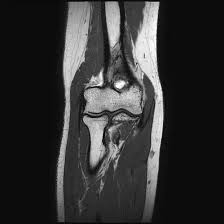

Medifyhome has collaborated with the best pathology laboratories that are NABL and NABH certified and follow ISO safety guidelines to provide the best MRI Screening Arm With Elbow at an affordable price for needy individuals. Magnetic Resonance Imaging (MRI) is a great and non-invasive medical tool that exploits the impacts of a magnetic field and radio waves in order to produce images of the human body from inside. MRI has been proved to be very effective in diagnosing conditions of the arm and elbow that involve bones, joints, muscles, tendons and other soft tissues. The arm and elbow together are used in almost all activities in our lives, and any problem that may affect this part of our body is likely to bring us much pain or limit the flexibility of our movement or use.

This service is essential if you have a regular ache, rigidity, inflammation, or if you have an injury the MRI is one of the paramount methods to find out what is going on with the arm and elbow. MRI of the arm and elbow are often applied in diagnosing forearm fractures, ligament or tendon strains, arthritis, nerve compressed, soft tissue injury, etc. Due to its great capacity for creating detailed and clear pictures of both the bones and the soft tissues, MRI assists health care professionals in coming up with correct diagnosis, choice of the right treatment and evaluation of the healing process. To schedule an appointment for MRI Screening Arm With Elbow, simply contact Medifyhome or call our customer care at +919100907036 or +919100907622 for more details and queries.